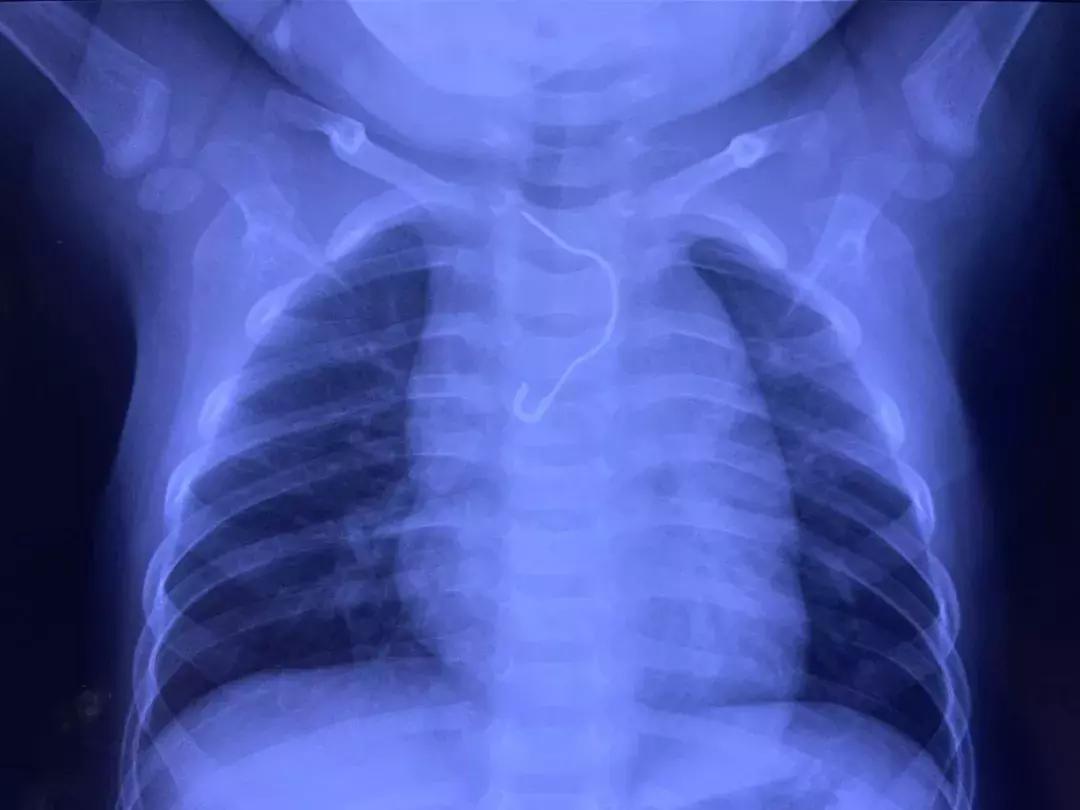

孩子妈妈立即将孩子送往当地医院进行检查,结果出来后,一家人直接懵了,别针确实是被孩子吞了进去,但当地并没有取出设备。医生建议将孩子送往河南省儿童医院接受治疗。

到达河南省儿童医院后,耳鼻喉科医师张红询问完病史后,立即向医院手术部申请急诊手术,为孩子取针。

下午4点30分,手术开始。姜岚与张红共同为孩子实施异物取出手术,姜岚将食管镜置入后,果然在食道1/3处“捕捉”到了别针。

最为危险的是,针头已经扎入在食道粘膜内。如果不能及时取出,随着食管和内脏的不断蠕动,别针很有可能刺穿胸壁造成食道穿孔、食管瘘,进而导致胸膜炎、败血症、感染性休克,甚至危及生命。